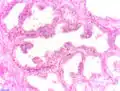

Invasion périneurale par un adénocarcinome prostatique. HE, x400

Anatomopathologie

Le cancer entreprend la portion périphérique de la glande, au contraire de l'hypertrophie prostatique bénigne qui intéresse la zone centrale, périurétrale.

La gravité de l'évolution est corrélée avec l'aspect microscopique (score de Gleason), le niveau de PSA et l'extension de la maladie[53].